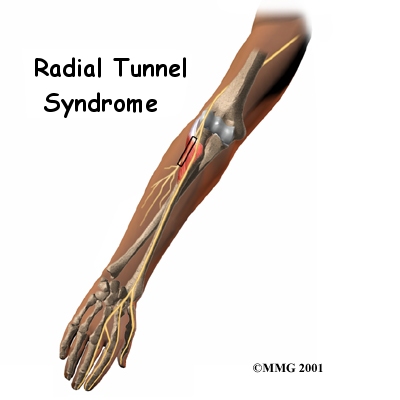

Radial tunnel syndrome happens when the radial nerve is squeezed where it passes through a tunnel near the elbow. The symptoms of radial tunnel syndrome are very similar to the symptoms of tennis elbow (lateral epicondylitis). There are very few helpful tests for radial tunnel syndrome, which can make it hard to diagnose.

On the lateral part of the elbow, the radial nerve enters a tunnel formed by muscles and bone. This is called the .

Pain is caused by pressure on the radial nerve. There are several spots along the radial tunnel that can pinch the nerve. If the tunnel is too small, it can squeeze the nerve and cause pain. Repetitive, forceful pushing and pulling, bending of the wrist, gripping, and pinching can also stretch and irritate the nerve.